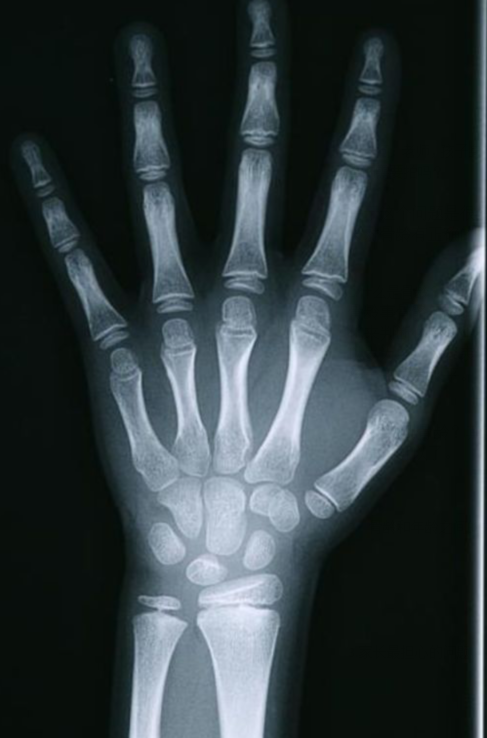

二,长骨的x线表现 1,小儿骨骼 小儿长骨可分为:骨干,干骺端,骺及 骺板

骨骺与骨干之间有一层软骨层,医学上称之为骺软骨 ( 骨骺线).